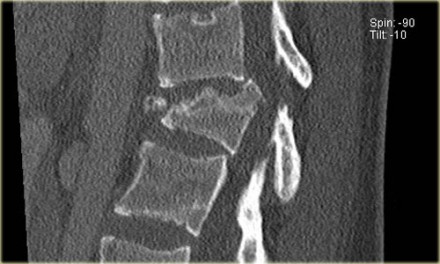

The images show a compression fracture.

All we see is a cortical disruption in the upper anterior wall of the vertebral body and slight loss of height ventrally.

The posterior vertebral cortex is intact.

The sagittal reformatted image also shows the cortical disruption.

Notice that on a 2.5mm axial slice you can miss these fractures.

You have to look at the thin slices to detect such a subtle fracture.

Notice the horizontal band of density, which is often described as sclerosis.

This density does not mean that it involves an older fracture that is already healing with sclerosis.

This is merely a sign of trabecular impaction in an acute fracture.